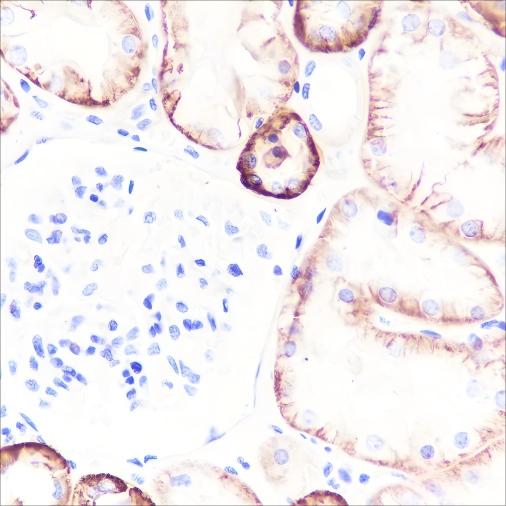

Verified Samples in WB: HeLa, RAW264.7, C6, Mouse brain, Rat brain Verified Samples in IHC: Human cervical cancer, Human kidney Verified Samples in IF: Jurkat, LNCaP |

| Dilution | WB 1:500-1:2000, IHC 1:200-1:1000, IF 1:50 |